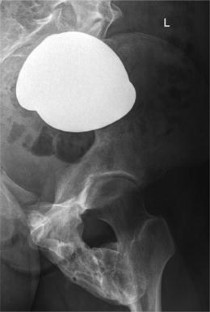

Fibrodysplasia ossificans progressiva (FOP) is a rare genetic disorder and the most disabling condition of heterotopic (extraskeletal) ossification in humans. Extraskeletal bone formation associated with inflammation preceding the osseous conversion usually begins in the first decade, predominantly in the head, neck, and shoulders. All patients have malformed great toes. Most patients have a spontaneous mutation of the ACVR1 gene. We report a 17-year-old girl with malformed great toes who had her first episode of heterotopic ossification and impaired mobility of the left hip at the age of 13 years. No inflammatory fibroproliferative masses preceded the onset of heterotopic ossification. Radiographic studies demonstrated myositis ossificans, but failure to associate the great toe malformation with heterotopic ossification led to a failure to diagnose FOP. She underwent repeated and unnecessary operative procedures to remove a recurrent lesion. FOP was finally suspected when the great toe malformation was correlated with the trauma-induced heterotopic ossification. Genetic analysis confirmed the presence of the classic FOP mutation (ACVR1 c.617G>A; R206H). This case highlights the importance of examining the great toes in anyone with heterotopic ossification. The association of malformations of the great toe with heterotopic ossification in all cases of classic FOP will lead to prompt clinical diagnosis and the prevention of iatrogenic harm.

Fig. 1